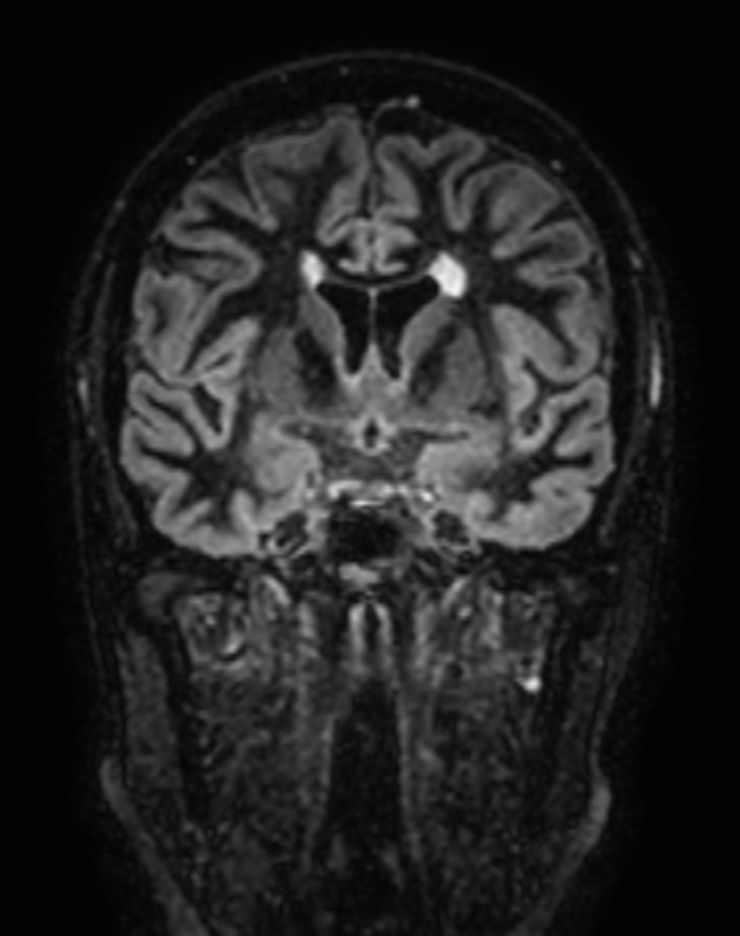

Multiple Sclerosis versus TIA

Standardized Multiple Slerosis MRI protocols typically require long scan times. Addition of Compressed SENSE enables faster exams, without compromise in image quality1. SWIp sequence has a high sensitivity to enhance contrast for deoxygenated (venous) blood or calcium deposits. This may help, when used in combination with other clinical information, in the diagnosis of various neurological pathologies. 3D (BrainVIEW) lets you acquire high resolution data in multiple directions in one scan. Isotropic voxel size enables reformats in any plane without loss of resolution.

3D T2w FLAIR BrainVIEW Compressed SENSE

3D T2w FLAIR BrainVIEW (reformat) Compressed SENSE

-